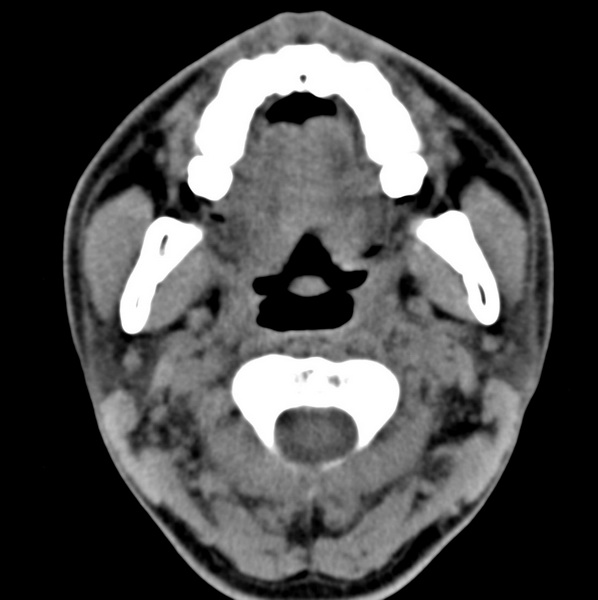

男、31、鼻咽部肿瘤放疗后请帮忙看看。

效果好,右侧破裂孔扩大,局部骨质缺损,为颅底骨质破坏。

1)鼻咽部肿瘤侵犯颅底放疗术后改变。2)左侧蝶窦炎。

咽后壁增厚,左侧咽鼓管隆突增大、咽鼓管咽口变浅,同侧咽旁间隙较窄。右侧颅底骨质破坏?为什么不在同一侧?

鼻咽部肿瘤侵犯颅底放疗术后改变.